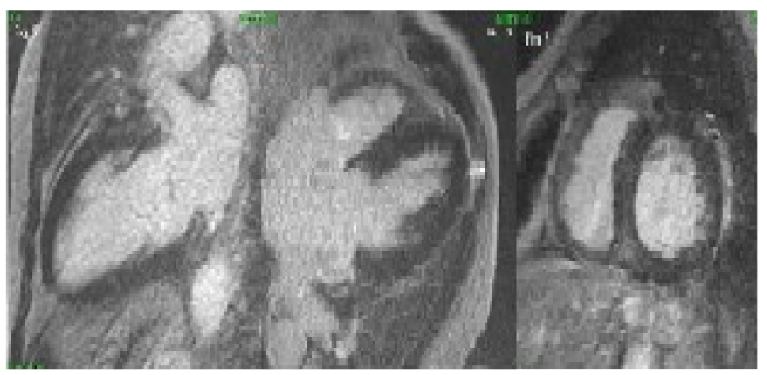

Al seguimiento de Cardiología, en vista de no tener enfermedad coronaria aguda, se indicó descartar miocardiopatía infiltrativa a través de una resonancia magnética (RMN) cardiaca con contraste (figura 4), la cual fue negativa, por lo que se requirió hemodiálisis antes y después del procedimiento, de acuerdo con las pautas por Nefrología. En este momento el paciente estaba estable y no congestivo, por lo cual con el esquema de hemodiálisis ya prescrito y el manejo para falla cardiaca ya establecido, se indicó el alta médica con diagnóstico de SCR tipo 4.

También se descarta una miocardiopatía infiltrativa por resonancia cardiaca, a pesar de no presentar antecedentes de enfermedad amiloide. Las formas adquiridas de amiloidosis cardiaca sugieren a la terapia de reemplazo renal como asociada a la aparición de la forma amiloide Aβ2M por mal plegamiento de la microglobulina β2. A su vez, el uso de la resonancia también permitió evaluar la función ventricular y la presencia de fibrosis miocárdica, la cual se puede presentar por la inflamación y el estrés oxidativo en el compromiso cardiaco por uremia, al tener en cuenta que esta avanza paralelamente a la falla renal y cardiaca (14, 24, 25).